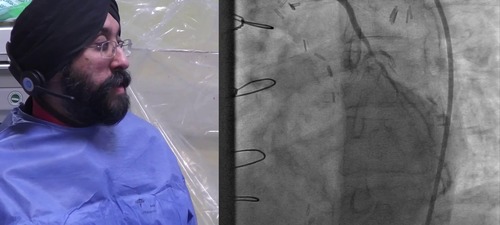

Amarjit Sethi presents interactive live case from the Hammersmith Catheter Labs.